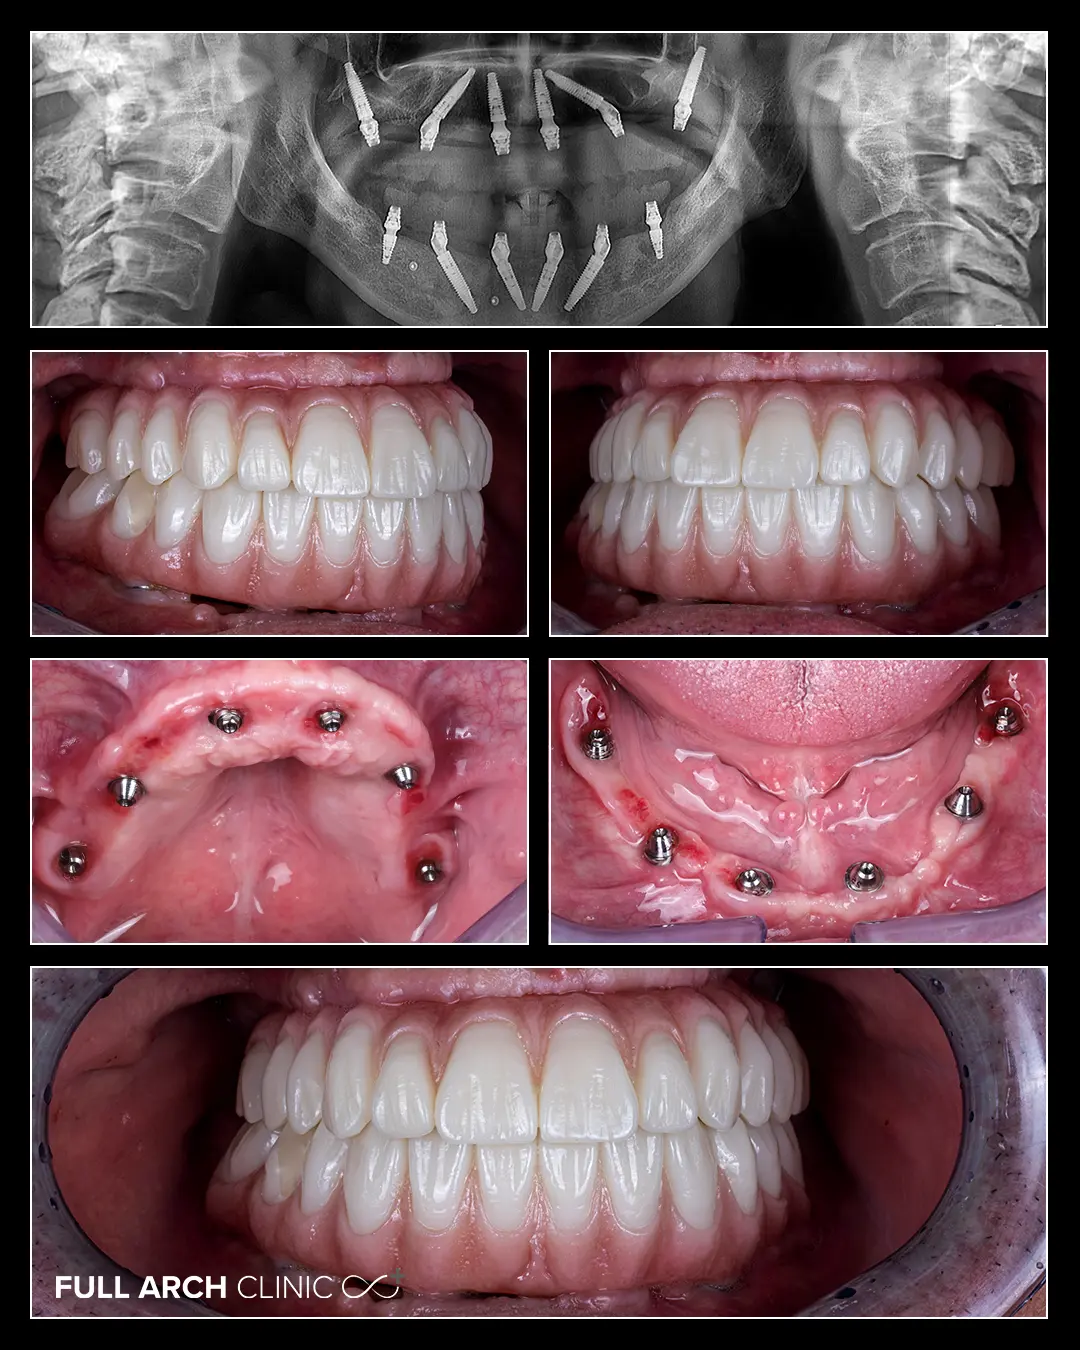

Domnul Ioan a amânat ani de zile tratamentul dentar | din frică și din cauza experiențelor neplăcute din trecut. A ajuns la noi din Israel, cu doar 2 dinți pe arcada inferioară și 7 dinți foarte mobili sus, afectați de parodontoză. A primit 12 implanturi și dantura fixă din zirconiu pe ambele arcade.

1. Arcada superioară (maxilar): 7 dinți rămași, toți afectați sever de boala parodontală:mobilitate avansată, pierdere osoasă semnificativă, imposibilitatea de a susține o lucrare protetică convențională

2. Arcada inferioară (mandibulă): doar 2 dinți rămași, cu infecții active, pe care era ancorată o proteză mobilă instabilă

Niciun dinte nu mai putea fi salvat. Indicația clinică era clară: extracția tuturor dinților rămași și reabilitare completă bimaxilară pe implanturi.

2. Inserarea a 12 implanturi dentare (10 implanturi convenționale și 2 implanturi pterigoidiene)

Am inserat câte 6 implanturi pe fiecare arcadă, un protocol All-on-6 bimaxilar. Implanturile au fost pozitionate strategic pentru a distribui uniform forțele masticatorii și a asigura stabilitate pe termen lung, chiar și în zonele cu pierdere osoasă cauzată de parodontoza avansată.

După perioada de osteointegrare, am trecut la etapa protetică finală. Am realizat toate probele necesare, funcționale și estetice, pentru a ne asigura că noile lucrări definitive din zirconiu sunt cât mai aproape de dinții naturali. Zirconiul oferă rezistență mecanică superioară și o estetică naturală.

Astăzi, domnul Ioan are dantura fixă pe ambele arcade, lucrări definitive din zirconiu fixate pe 12 implanturi. Schimbarea este vizibilă și semnificativă: fizionomia s-a transformat, zâmbetul este natural, iar capacitatea de a mânca, vorbi și zâmbi fără restricții a fost complet restaurată.

Diferența față de lucrările provizorii a fost perceptibilă imediat. Zirconiul este mai greu, mai rezistent mecanic și cu o estetică superioară față de polimerul provizoriu. Pacientul îi simte ca pe dinții lui naturali.